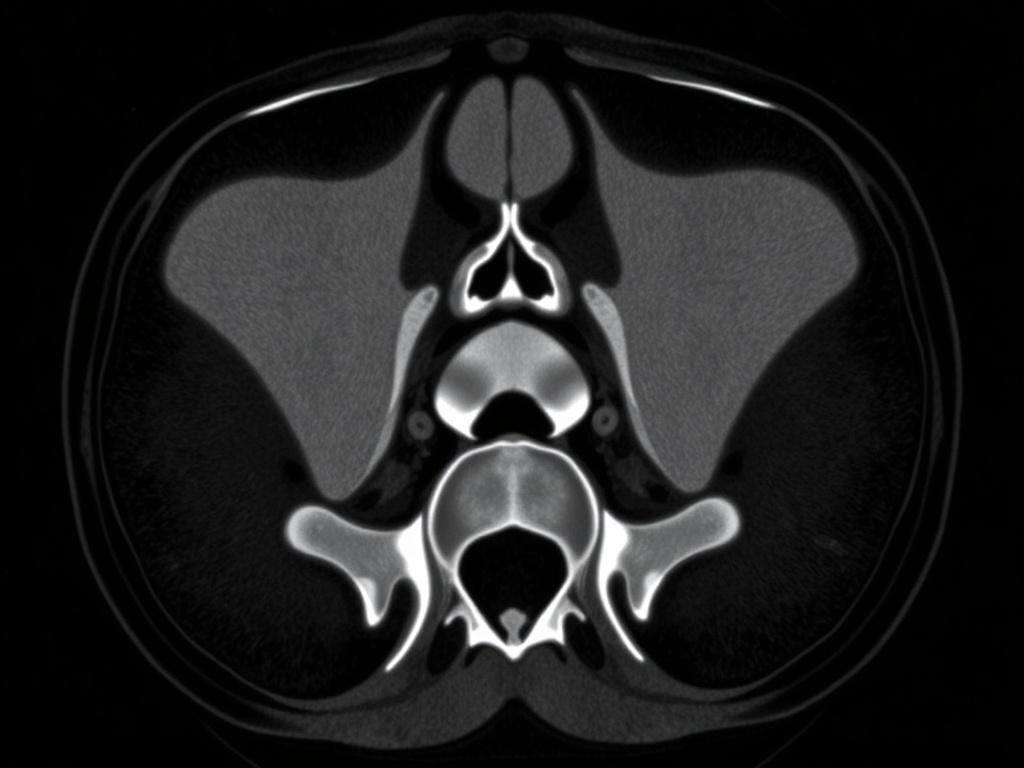

Компьютерная томография — это послойная рентгеновская съёмка, которая создаёт детальные снимки структур внутри тела. КТ копчика фокусируется на нескольких позвонках в области копчика и крестца. Сканер делает множество снимков под разными углами, компьютер объединяет их в объёмное изображение, которое можно рассматривать по срезам.

Главное преимущество КТ — высокая детализация костных структур. Если нужно увидеть трещину, перелом, деформацию суставов или костные фрагменты, КТ справляется лучше, чем обычный рентген. С другой стороны, мягкие ткани видно хуже, чем на МРТ.

Что видно на КТ копчика: типичные находки

КТ особенно информативна при оценке костей. Ниже таблица с наиболее частыми находками и их значением для диагностики и лечения.